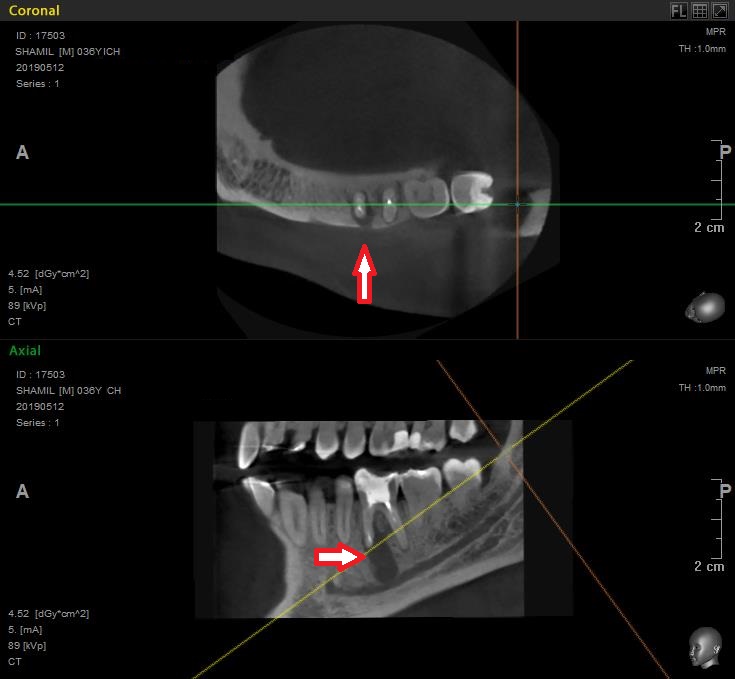

На этом снимке видно, что вокруг корня зуба образовалась киста, которая заполнена кровяной массой.

Если всмотреться в этот снимок, то можно увидеть участок, где киста пробила кость. Именно это и стало причиной болей и воспаления на челюсти.

Киста — защитная реакция организма, с помощью которой организм отгораживается о проблемного зуба. Первичная причина возникновения проблемы – сломанный фрагмент инструмента, который остался в зубе, при лечении его 19 лет назад. Оставшийся в зубе инструмент создает условия для воспалительного процесса.

На этой проекции видно повреждение поверхности кости от кисты.

(отверстие, которое вы видите слева, чуть ниже — место выхода нижнечелюстного нерва)